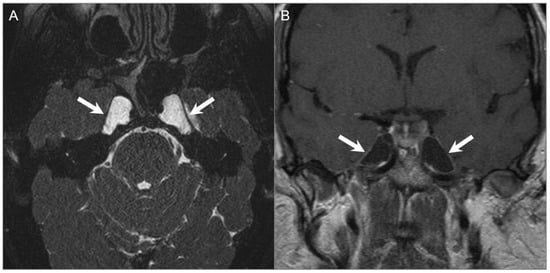

5.2. Asymmetric Petrous Apex Pneumatization

5.3. Arachnoid Granulations